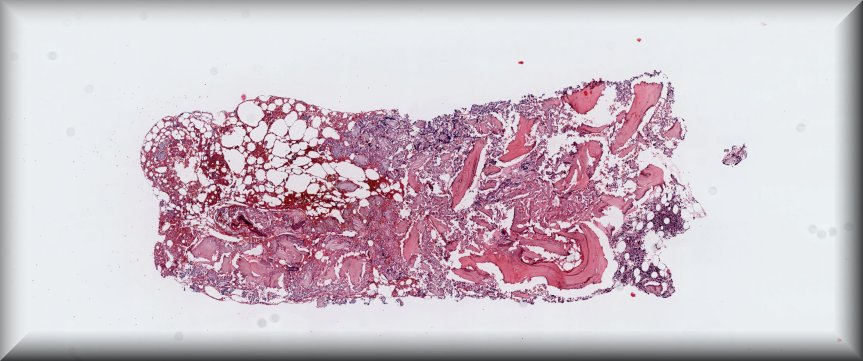

Caso 4.- Paula Tenhaeff Lackschewitz, Gerónimo Llopis, Raquel Martínez Marcos, Esther Roselló Sastre.

Hospital General Universitario de Valencia.

Varón de 28 años, con antecedente de infección por VIH diagnosticada en 2019 y abandonodel tratamiento antirretroviral. Consulta por un mes de evolución de lesiones cutáneas pápulo-nodulares eritematosas y descamativas, tos seca, pérdida ponderal de 10 kg y edemas enextremidades inferiores. En la exploración presenta fiebre de 39 °C, taquicardia y hepatoesplenomegalia. La analítica muestra pancitopenia severa, hipoalbuminemia,hipertransaminasemia y ferritina >90 000 µg/L. Serologías para VHB, VHC, CMV, VEB yBartonella negativas, con beta-D-glucano positivo. Con sospecha de leismaniasis/linfoma serealiza biopsia de médula ósea.